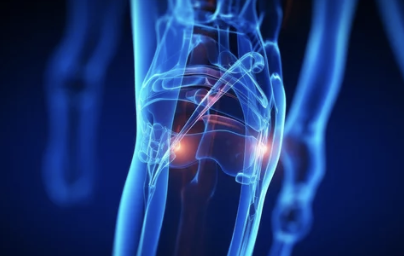

무릎 연골은 뼈와 뼈 사이에서 완충 작용을 하여 관절의 부드러운 움직임을 돕고, 마찰을 줄여주는 역할을 해요.

- 연골의 종류: 무릎에는 반월상 연골과 관절 연골, 두 가지 종류의 연골이 있어요. 반월상 연골은 무릎 안쪽과 바깥쪽에 C자 모양으로 위치하며, 충격 흡수와 안정성 유지에 중요한 역할을 합니다. 관절 연골은 뼈 끝 부분을 덮고 있으며, 뼈끼리 부딪히는 것을 막아주고 부드러운 움직임을 가능하게 해요.